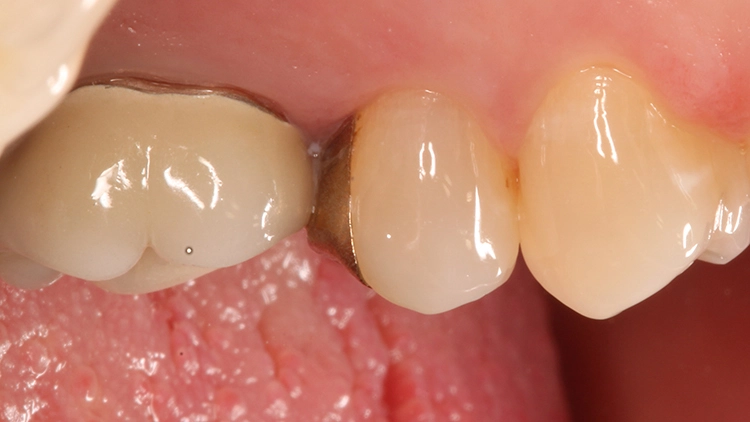

Da aufgrund der Randdefekte eine Austauschindikation bestand, wurden das Inlay sowie minimale Restkaries entfernt und die Ränder nachpräpariert. Bei einer direkten Komposit-Neuversorgung können im Gegensatz zu einer Neuversorgung mit einem Keramikinlay spitz auslaufende Ränder in Form des alten Federrandes belassen werden, da das Restaurationsmaterial diese Bereiche ausfließen und somit randdicht versorgen kann.

Nach Entfernung des Goldinlays zeigte sich eine kariesfreie Kavität, die lediglich nachfiniert werden musste. Im Zuge dieses Arbeitsschrittes wurde auch die Klebefläche angefrischt. Aufgrund der vorangegangenen Federrandpräparation ergab sich eine für eine Keramikversorgung (die als Alternative diskutiert worden war) sehr ungünstige Gestaltung des approximalen Kastens.

Ein Nachpräparieren in Richtung einer planen Stufe würde den approximalen Kasten unnötig vertiefen. Ein zervikaler Aufbau in Form einer Kavitätenbodenelevation [13,15,24–26] würde dieses Problem zwar lösen, aber dann auch die berechtigte Frage aufwerfen, warum bei einem so klein dimensionierten Defekt der Rest der Kavität nicht auch gleich mit Komposit versorgt wird.